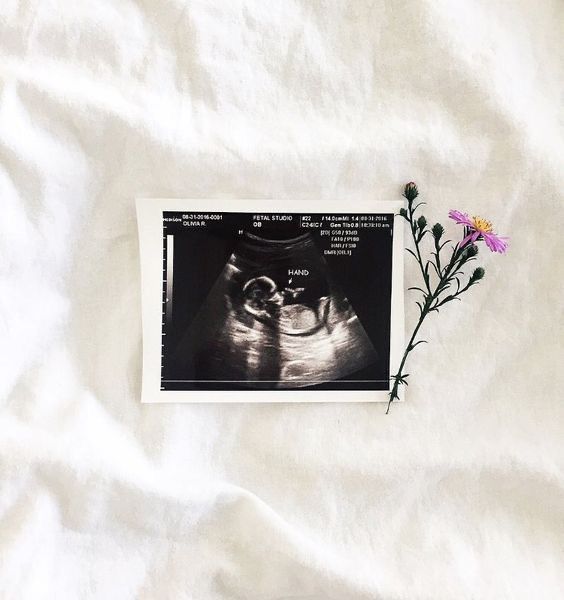

01.jpg 인스타그램 연재글 @woodumi

사진출처 ⓒ핀터레스트